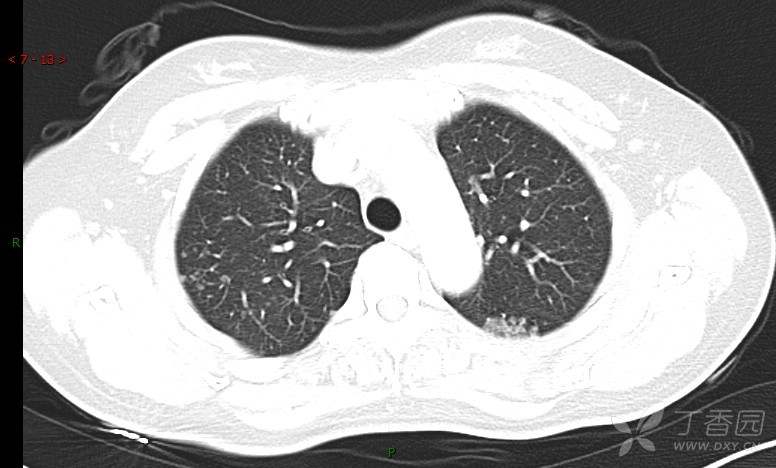

腺泡结节影,蜂窝征,这些都在提示……(病例3连发,附其他2例链接,病理已公布)

咳嗽1年余,加重7天。

患者于1年余前始受凉后出现咳嗽,多为干咳,未在意,未到医院就诊。近3月患者出现咳痰,多为黄色粘痰,量大,伴乏力,偶有头晕、心慌,无发热、胸痛、憋喘,无低热、盗汗、咯血、胸痛,无头痛,无恶心、呕吐、腹痛、腹泻,无尿频、尿急、尿痛,在当地诊所给予抗感染等对症支持治疗(具体药物及剂量不详),症状仍时有反复。患者于1月余前到外院就诊,行胸部CT提示双肺炎症,左肺重,考虑为“间质性肺炎”,给予“左氧氟沙星、利巴韦林、头孢哌酮舒巴坦钠注射液”治疗,复查胸部CT示病灶吸收不理想,后出院继续于诊所对症治疗(具体药物及剂量不详),效果欠佳。7天前患者无明显诱因出现上述症状加重,为求进一步诊治,特来我院就诊,我院门诊以“肺炎(重症)?”收入留观室,留观室给予“盐酸莫西沙星氯化钠”等对症治疗后,今日转入我科。患者自发病以来,神志清,精神差,饮食正常,睡眠增多,大小便正常,体重近3月减轻5公斤余。